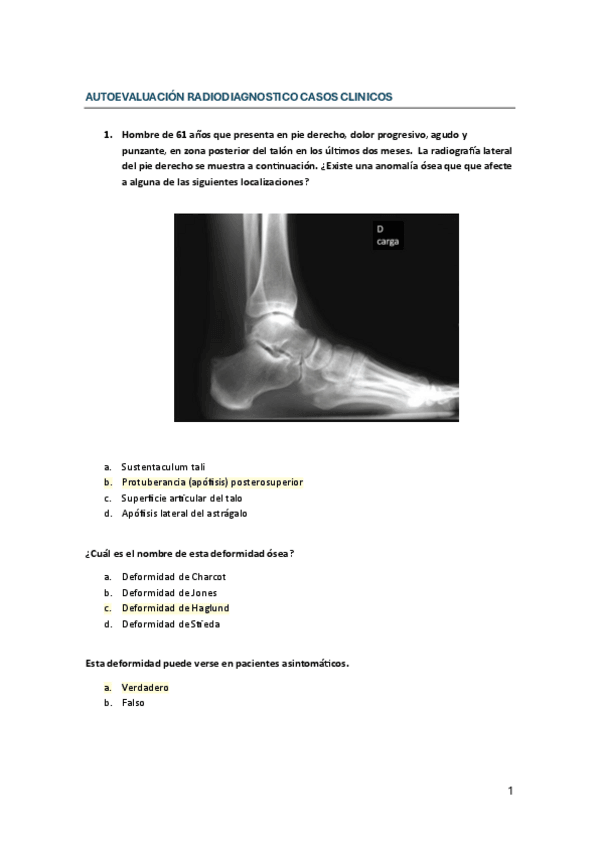

He publicado nuevos examenes de 3º Radiodiagnóstico y radioprotección: AUTOEVALUACION-RADIODIAGNOSTICO-CASOS-CLINICOS.pdf

28 páginas